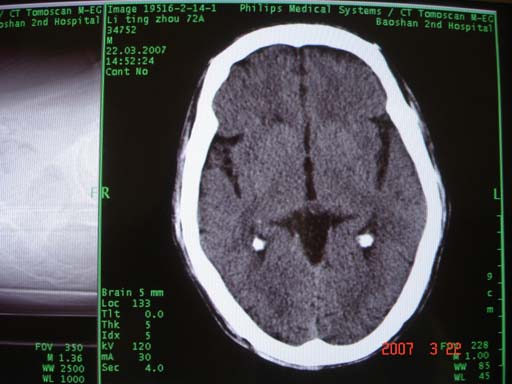

我是新手,用数码相机照下来的图片,向大家请教:以下的图片正常还是异常(是什么病?)?谢谢

双侧脉络膜裂囊肿?不放心作个mri看看。

图片是正常的(或结构变异--还是多见的)

可考虑侧脑室颞角。脉络膜裂待排。 建议mri

考虑:脉络裂囊肿。建议行mri检查!

3、脉络裂囊肿ct表现 ①发生侧别:本组发生于右侧者明显多于左侧;②具有蛛网膜囊肿的一切特征:病灶边界清、圆形或椭圆形、密度均匀、与脑脊液密度相近等;③部位:位于颞叶内侧海马与间脑之间的脑脊液间隙内,病灶最大层面一般位于大脑脚上部或中脑与间脑移行区水平,囊肿的周围可见灰质结构。

4、脉络裂囊肿的mri表现 mri冠状位可显示囊肿位于脉络裂内,其外下方可见侧脑室颞角呈点状或条状结构,矢状面显示颞叶内侧卵圆形或纺锤形囊肿,为特征性表现,有利于作出诊断。

鉴别诊断

1、脉络裂囊肿与侧脑室颞角的鉴别 脉络裂囊肿位置接近侧脑室颞角,二者容易被互相误诊,ct轴位扫描显示囊肿中心层面的位置高于侧脑室颞角最大层面的位置,侧脑室颞角从外侧绕过囊肿向前、内、下走行,上下层面不同二者之间相对位置也不同,可资鉴别。mri冠状位显示囊肿位于海马上方,而颞角位于海马外侧,利于明确诊断。

2、脉络裂囊肿与脑内病变的鉴别 当病灶较小时,有容积效应存在,易被误诊为脑梗死。当病灶较大,密度接近脑脊液时,易被误诊为脑软化灶,脑梗死及软化灶多发生于基底节区层面,而脉络裂囊肿常出现于基底节区下方层面。mri冠状位扫描是鉴别二者的最佳方法。

3、脉络裂囊肿与环池内囊性病变的鉴别 发生于脉络裂内侧部的囊肿靠近环池,易被误诊为环池的病变,如环池蛛网膜囊肿,胆脂瘤等,环池囊性占位有明显脑干受压征象,且邻近环池扩张,可资鉴别。

支持脉络裂囊肿,只是双侧如此对称发生少见。

双侧基底节区有对称性低密度影,不能说正常

双侧对称性表现,是否应多考虑正常变异,病变能如此对称,应该是少之又少。这种表现笔者遇到多例,难道都是脉络裂囊肿吗